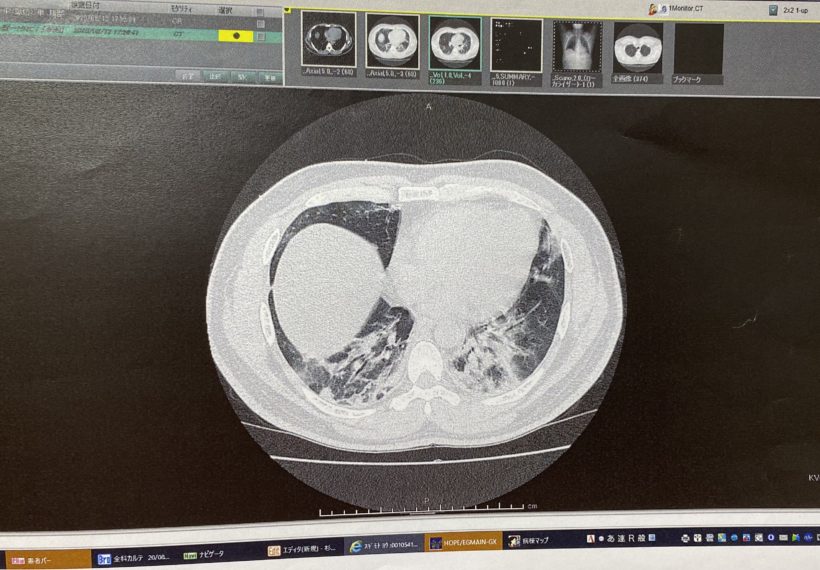

一部の方にはご報告させて頂いておりますが、私は2020年8月にCOVID-19に罹患し、死の淵を覗きながら生還に至っています。

そこで患者として・・・と同時に、患者さんを扱う施術を行う身としての目で、実際の医療現場を見てきました。

私自身の症状のカテゴリーは、行政では「中症状」しかし、臨床医学的は「重症」・・・こういった違いを始め、溢れているが精度の高い情報を纏めづらい現状を鑑みてオンラインセミナーを行います。